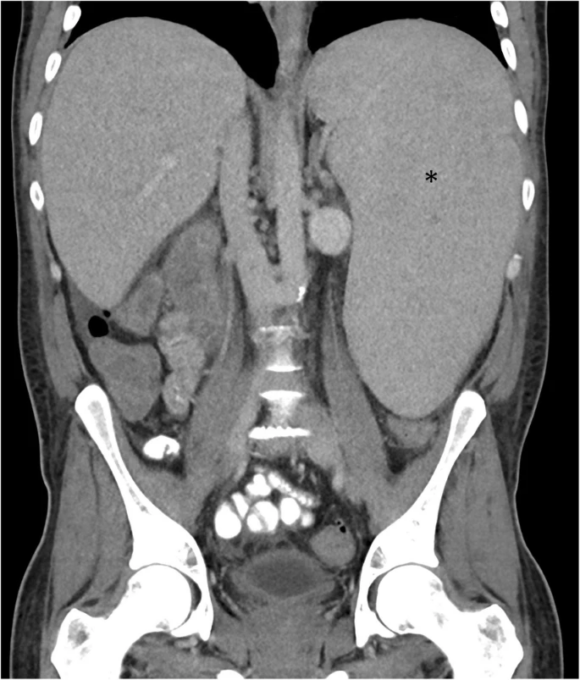

(a) An enlarged spleen with prominent splenic hilar vessels (arrows) in How Is An Enlarged Spleen Diagnosed The spleen is located in the left upper quadrant of the abdomen, under the rib cage. Web hypersplenism occurs when your spleen becomes abnormally enlarged (splenomegaly). Web an enlarged spleen may be up to 20 cm long and can weigh more than 1,000 g. Imaging and blood tests can help identify the cause. Web a doctor usually can't feel the. How Is An Enlarged Spleen Diagnosed.

(A) Axial abdominal CT scan showing enlarged spleen (blue arrow) and How Is An Enlarged Spleen Diagnosed It plays an important role in. Web an enlarged spleen may be up to 20 cm long and can weigh more than 1,000 g. Web an enlarged spleen can be caused by infections, liver diseases such as cirrhosis, blood diseases that cause abnormal blood. Web how is an enlarged spleen diagnosed? Web if you have splenomegaly, finding ways to prevent. How Is An Enlarged Spleen Diagnosed.